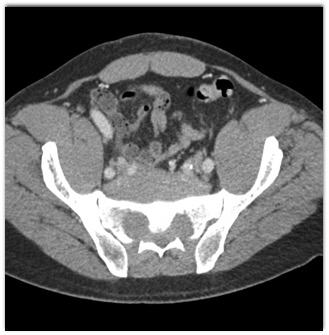

The best diagnosis in this case of a patient with back pain is?

extramedullary hematopoiesis

myeloma

lymphoma

Ewings sarcoma